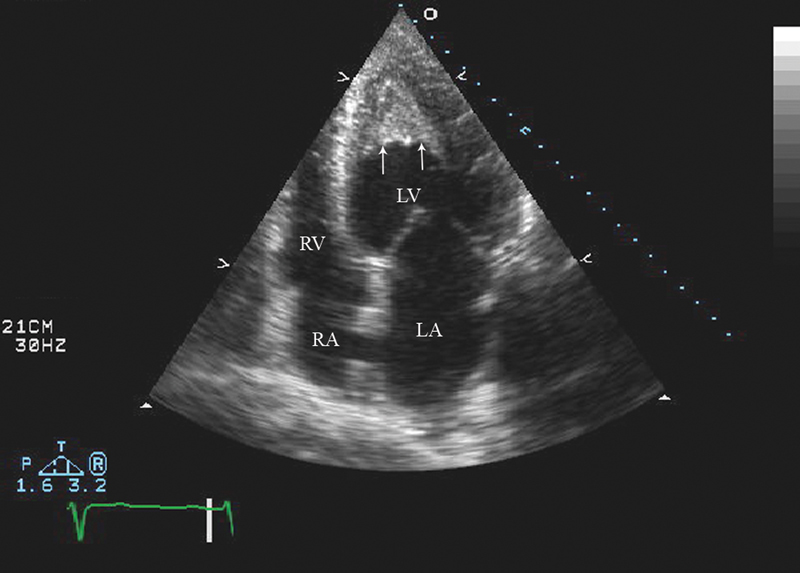

فحوصات تشخيصية لبعض امراض القلب والشرايين التاجية